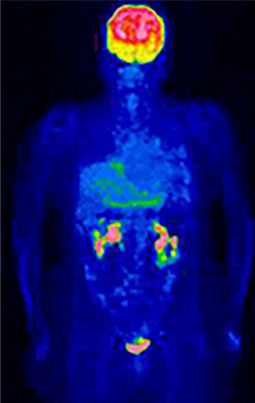

⑤治療中の方の効果判定に役立ちます

がんの治療には手術以外にも、化学療法や放射線療法など、さまざまな方法があります。従来はCTやMRI検査で、治療で効果が出たかどうかを見るのが一般的でしたが、治療後も異常陰影が残っていることがあり、がん細胞は残っているのか治ったあとの瘢痕なのかを判断できませんでした。

FDG-PET検査を用いるとがん細胞の活動性がわかるため、従来の検査より早い時期に、治療効果の判定をすることが可能です。治療効果判定はなるべく早く行うことで、速やかに次の段階の治療方針を検討することができます。

悪性リンパ腫